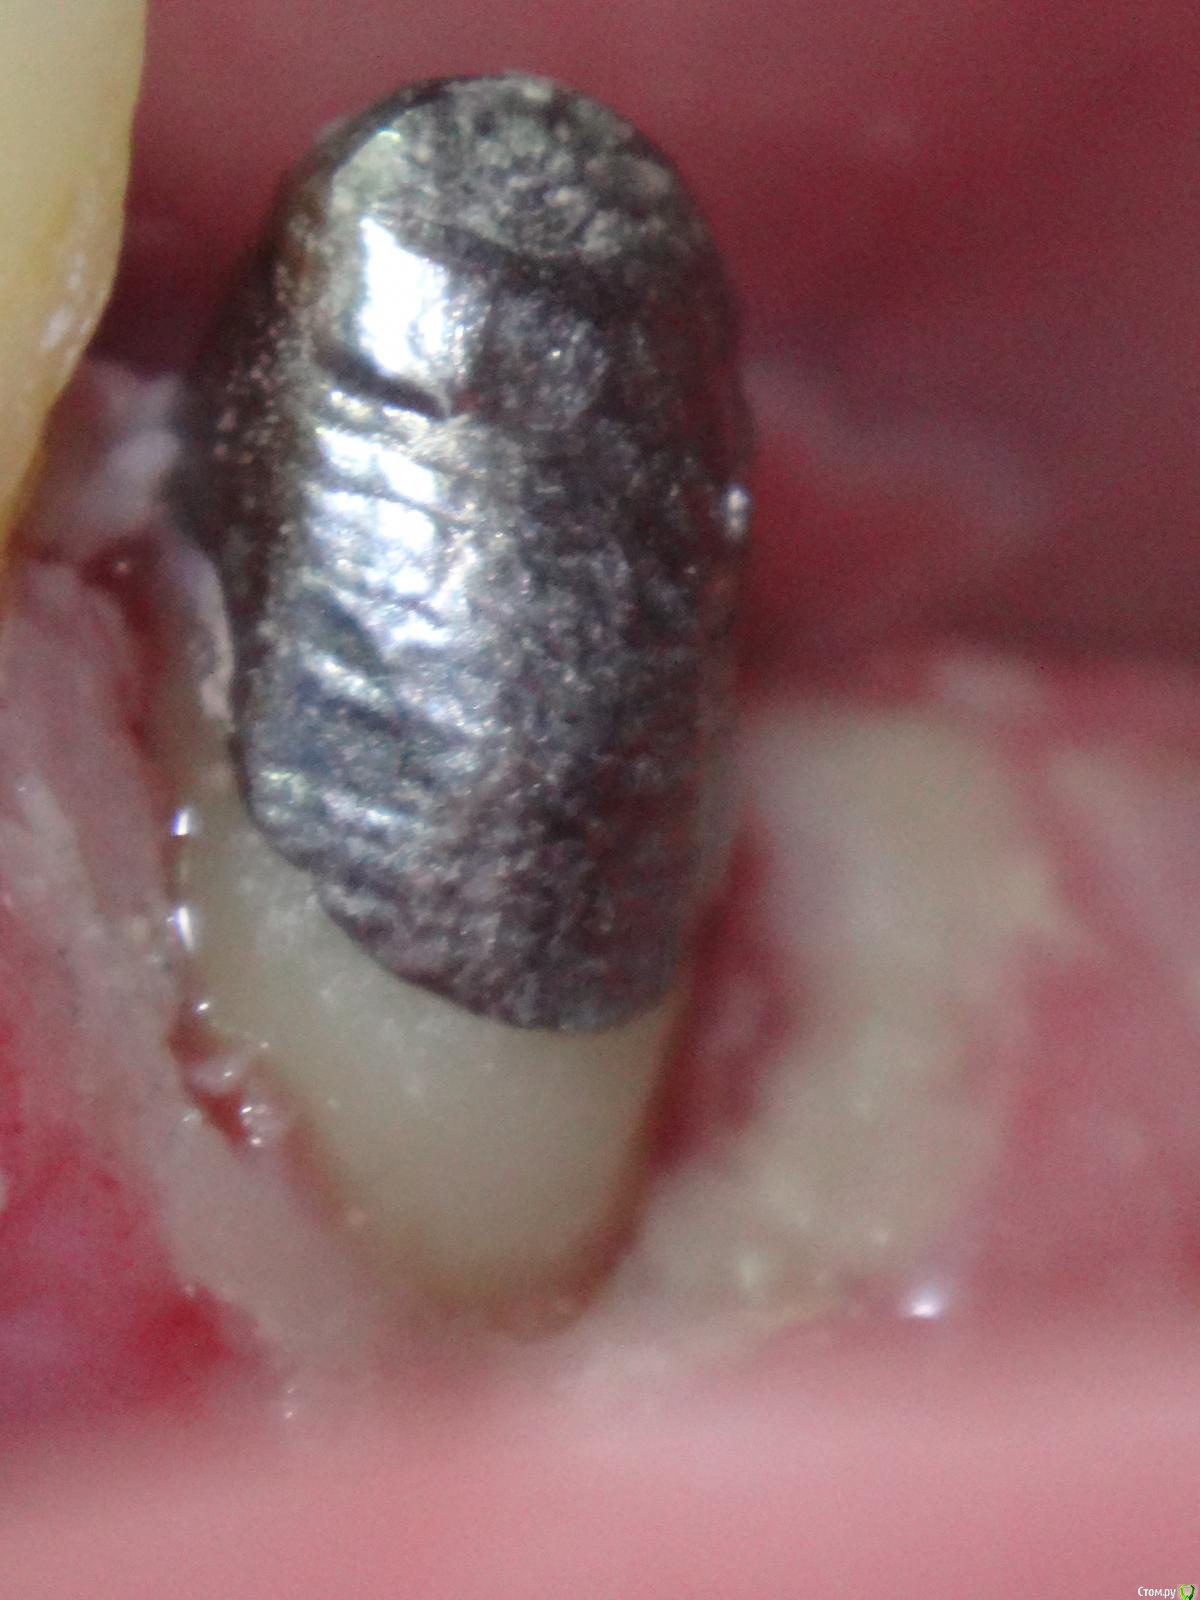

Slaggy Опубликовано 10 сентября, 2015 Поделиться Опубликовано 10 сентября, 2015 паттерн отлипает от стенок. Ему только застыть надо дать время. И кончики твердеют. Не спешите просто.Вазелины шмазелины снизят точность - как вы проконтролируете толщину слоя вазелина в глубине канала?Не пересушивайте канал и будет щастье вам.Вот вопрос чем извлекать вкладку после примерки возникает иногда. Садятся-то они без зазора.... пришло из лабы - ленивые удалено администратором литник не убрали даже, фуджи прилип немного в апроксималке, контрольповерхность завальцована ультразвуком - извлекал после примеркикорень был скрыт под десной- удлинял, отсюда такой вид По поводу врещения - есть 2 вида геморроя:1- паттерн застыл и вы извлекли недовкладку - будет вертеться при обработке, нужно придерживать2- паттерн застыл и сразу обрабатываем - сложно извлечь готовую вкладку не сделав на ней следавыбираем как сегодня будем страдать и начинаем ))))) 1 Ссылка на комментарий

Slaggy Опубликовано 10 сентября, 2015 Поделиться Опубликовано 10 сентября, 2015 Я много лет делал непрямым - был отличный техник, садилось все великолепно.Сейчас в лабе хорошее литье (на фото) и кривые руки (там-же), поэтому стал делать прямым.Точность одинаковая - цемент не виден по шву.Я часто уступ точу уже по вкладке, поэтому толщина/нависание края меня мало занимают. Ссылка на комментарий